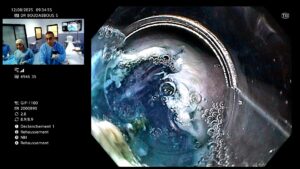

- Le médecin crée un tunnel sous la muqueuse œsophagienne.

- Il sectionne les fibres musculaires du SIO responsables de l’obstruction.

⏱️ Durée : Environ 2 à 3 heures